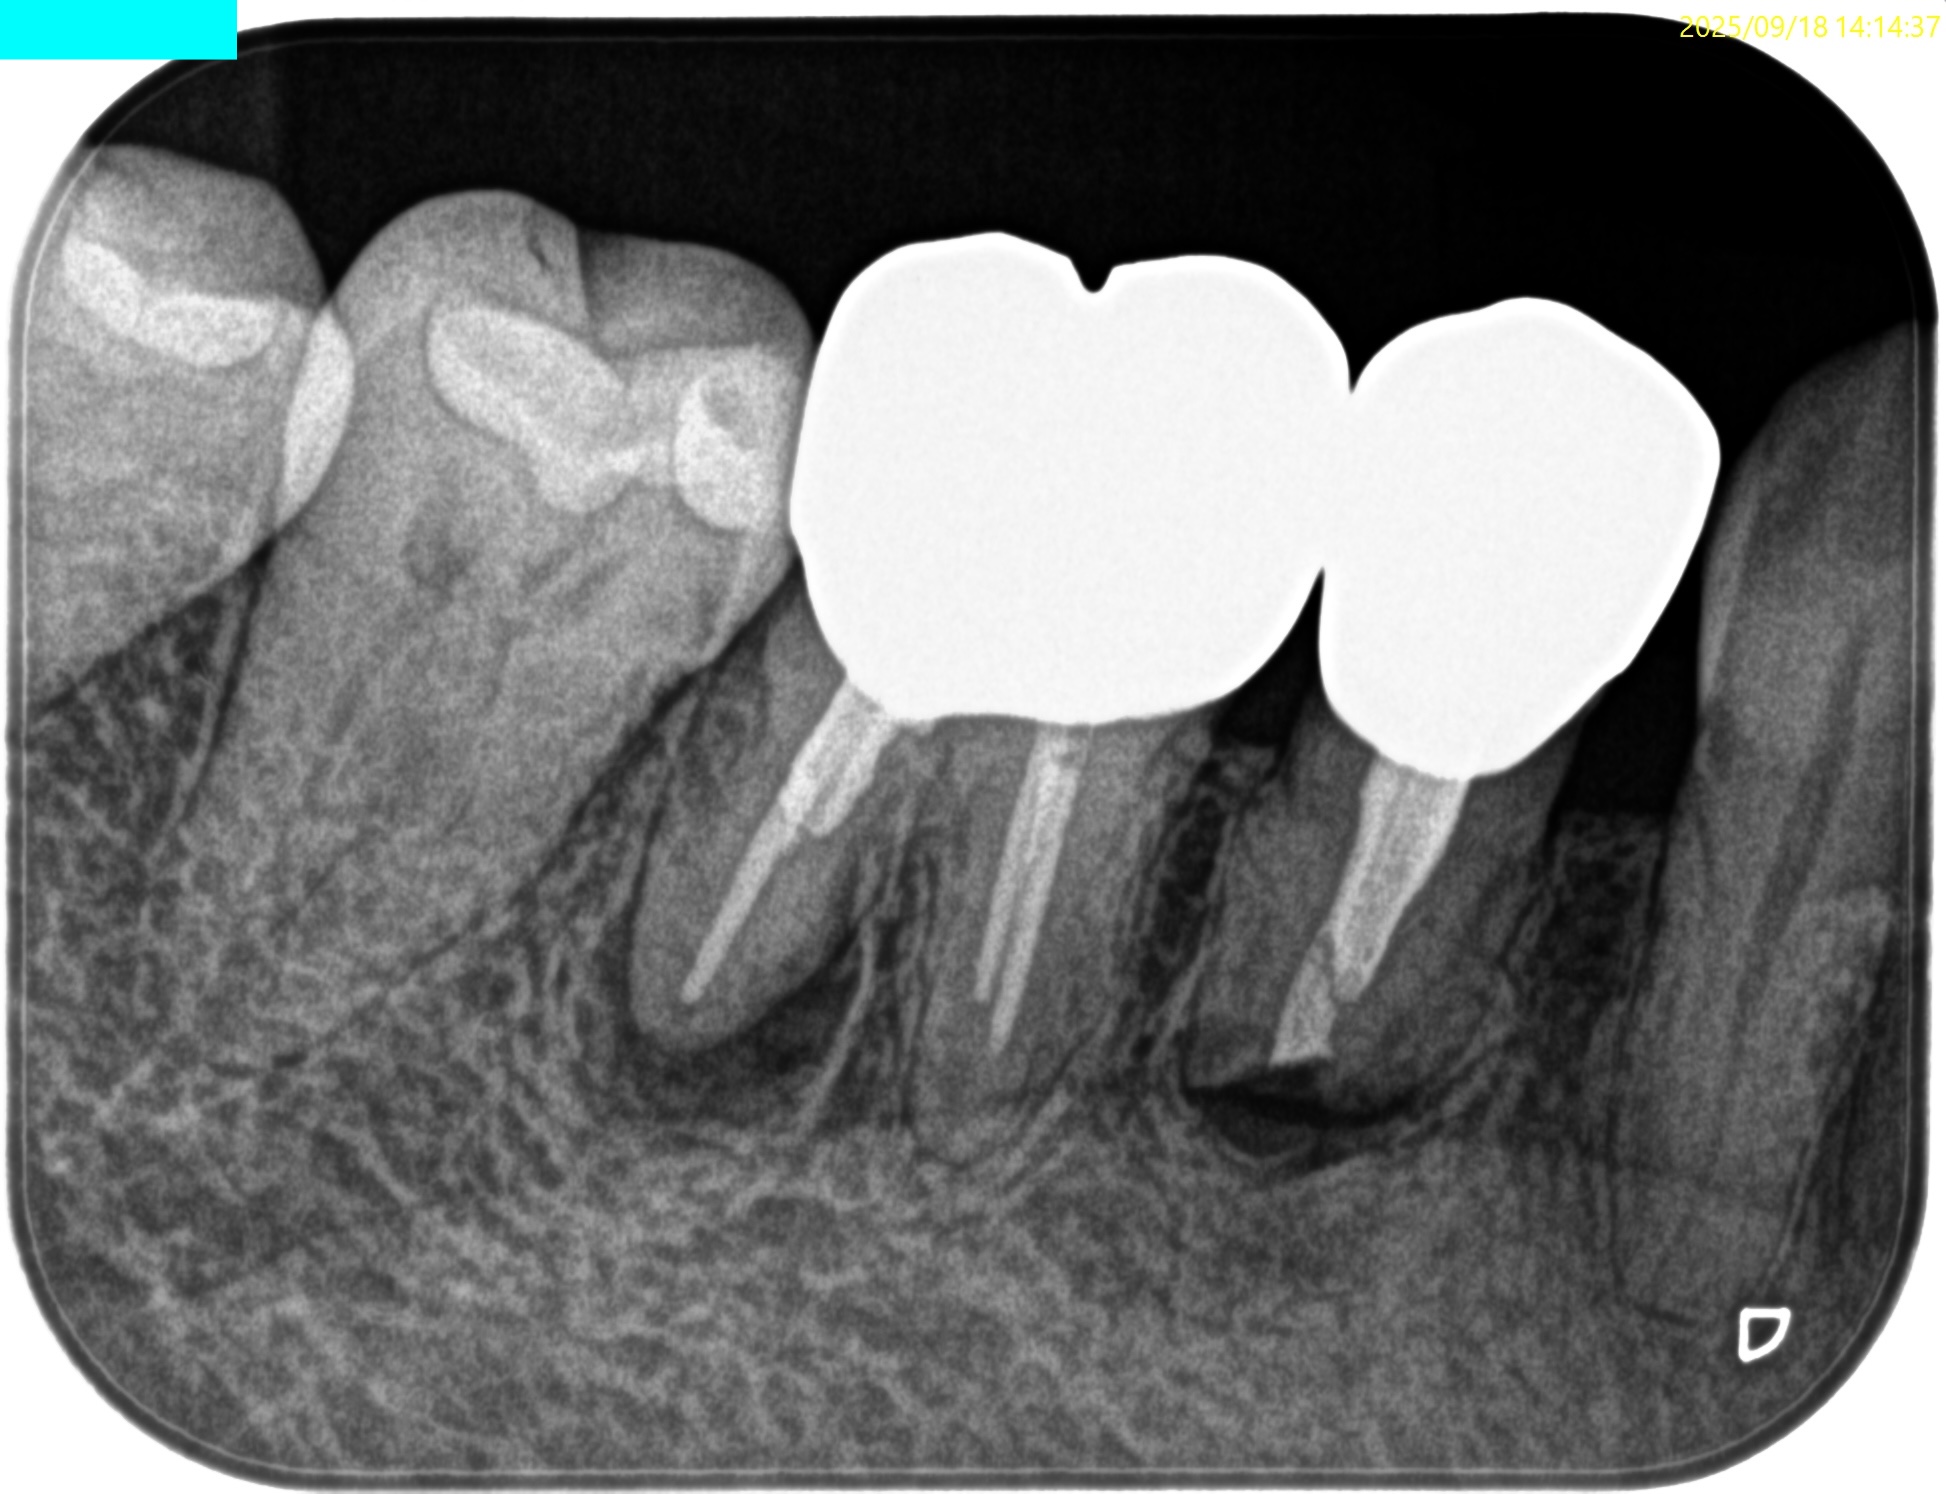

以前の治療の経過観察。

数年ぶりに患者さんが歯茎の腫脹で来院した。

PA, CBCTを撮影した。